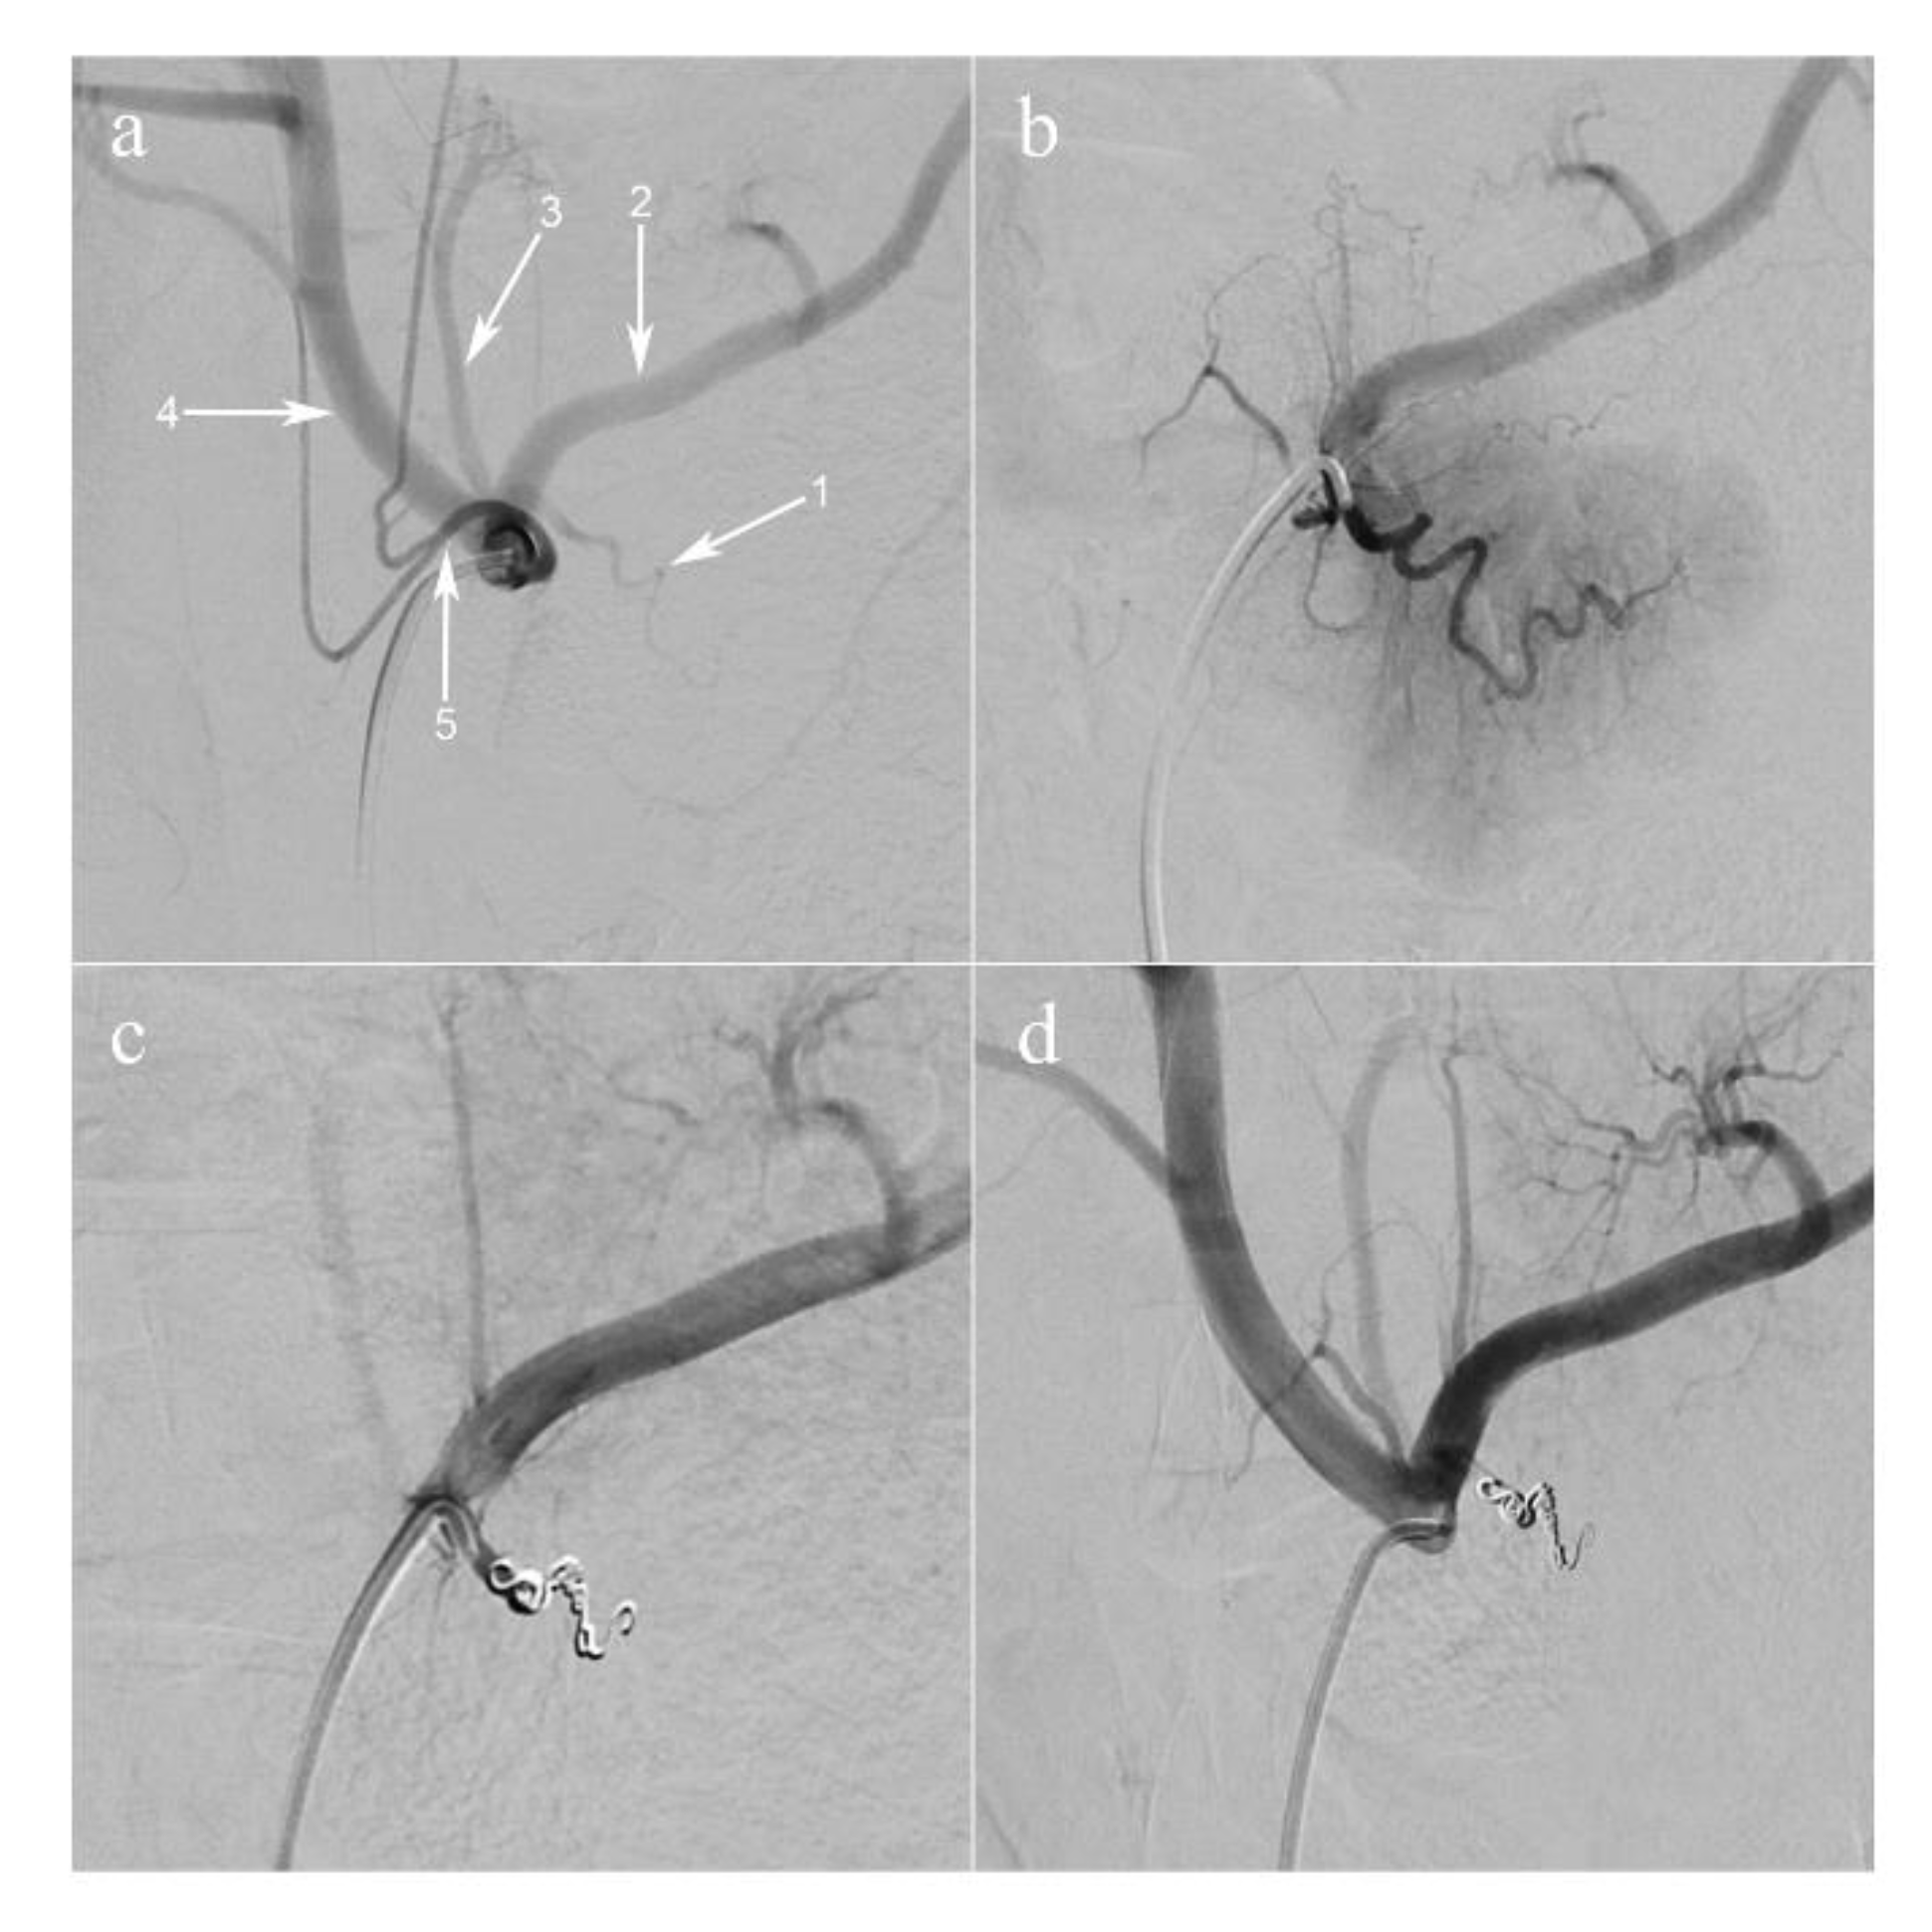

The main pancreatic branch of the splenic artery (equivalent to the dorsal pancreatic artery in humans) was selectively catheterized using a 2.8 French microcatheter (PROGREAT®, Terumo Europe NV, Leuven, Belgium). The artery was occluded using large volume 0.020-inch diameter coils (Ruby® Coils, Penumbra Inc., Alameda, CA USA), in order to obtain a selective ischemia of the pancreatic tail and part of the body ( Figure 1; Figure 2b).

Figure 1. Arterial coil embolization of pancreatic artery. (a) Selective injection of the celiac trunk (digital subtraction angiography, anteroposterior view). The dorsal pancreatic artery (1) is shown, branching off the proximal splenic artery (2); (3) the left gastric artery; (4) the common hepatic artery; (5) the common trunk of the left and right phrenic arteries. (b) Super-selective injection of the dorsal pancreatic artery. The parenchyma of the pancreatic tail is visualized. (c) The dorsal pancreatic artery is occluded with coils. (d) Selective injection of the celiac trunk post-embolization.

The endovascular procedures were successful (Figure 1) followed by imaging analyses (Figure 2a). Pancreatic ischemia could be obtained in all pigs (Figure 2b). Additionally, augmented reality (AR) of the overlaid HSI (Figure 2c) and FLER (Figure 2d) images was possible in all cases, and the virtual demarcation line between vital and ischemic zones was visually consistent in both imaging modalities (Supplementary Video). Besides, AR allowed for accurate confocal laser endoscopy (CLE) scanning, local lactate (LCL) sampling and biopsies, in correspondence with each ROI.